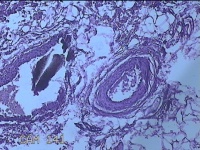

外阴部包块

性别

女

年龄

37岁

临床诊断

皮脂腺囊肿

一般病史

外阴部起包块一月余。

标本名称

大体所见

灰白暗红色包块2.3x1.8x0.8cm一个,表面糜烂,切开包块呈实性,切面灰白淡黄色,质软。

图2